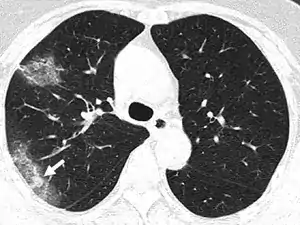

Silent hypoxia (also happy hypoxia)[1][2] is hypoxia that does not coincide with shortness of breath.[3][4][5] It is known to be a complication of coronavirus disease 2019.[6][7] It is speculated that this condition is caused by SARS-CoV-2 affecting the blood flow of the lungs' airways, in addition to the blood vessels within the lungs, which must match in order to allow proper airflow, but not affecting them enough to cause shortness of breath.[8][9] It is also speculated that silent hypoxia may be caused by the formation of small blood clots within the lungs.[10][11][12] It has been shown that the breathing rates of patients with COVID-19 gradually increase, which in turn leads to silent hypoxia.[13] It has also been shown that COVID-19 patients experience lesser levels of shortness of breath after exercise than non-COVID-19 patients.[14] The condition is also known to be caused by walking pneumonia[15] and altitude sickness.[16][17][18]